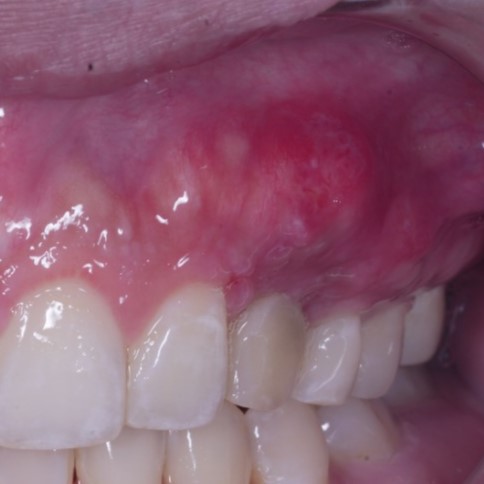

I would be interested to see what an intraoral photo of the implant looks like. I invite you to share if you have one!

Hello Ivan, thank you for your reassurance. Here are some of the post operative one week photos. Good thing is patient has a low lip line. And yes, I could not relly see any exposure and I did place some bone graft with straumann xenoflex at the apical region. Have a great weekend !

The gingiva biotype looks thick type so, I don’t think you will have problem with the implant